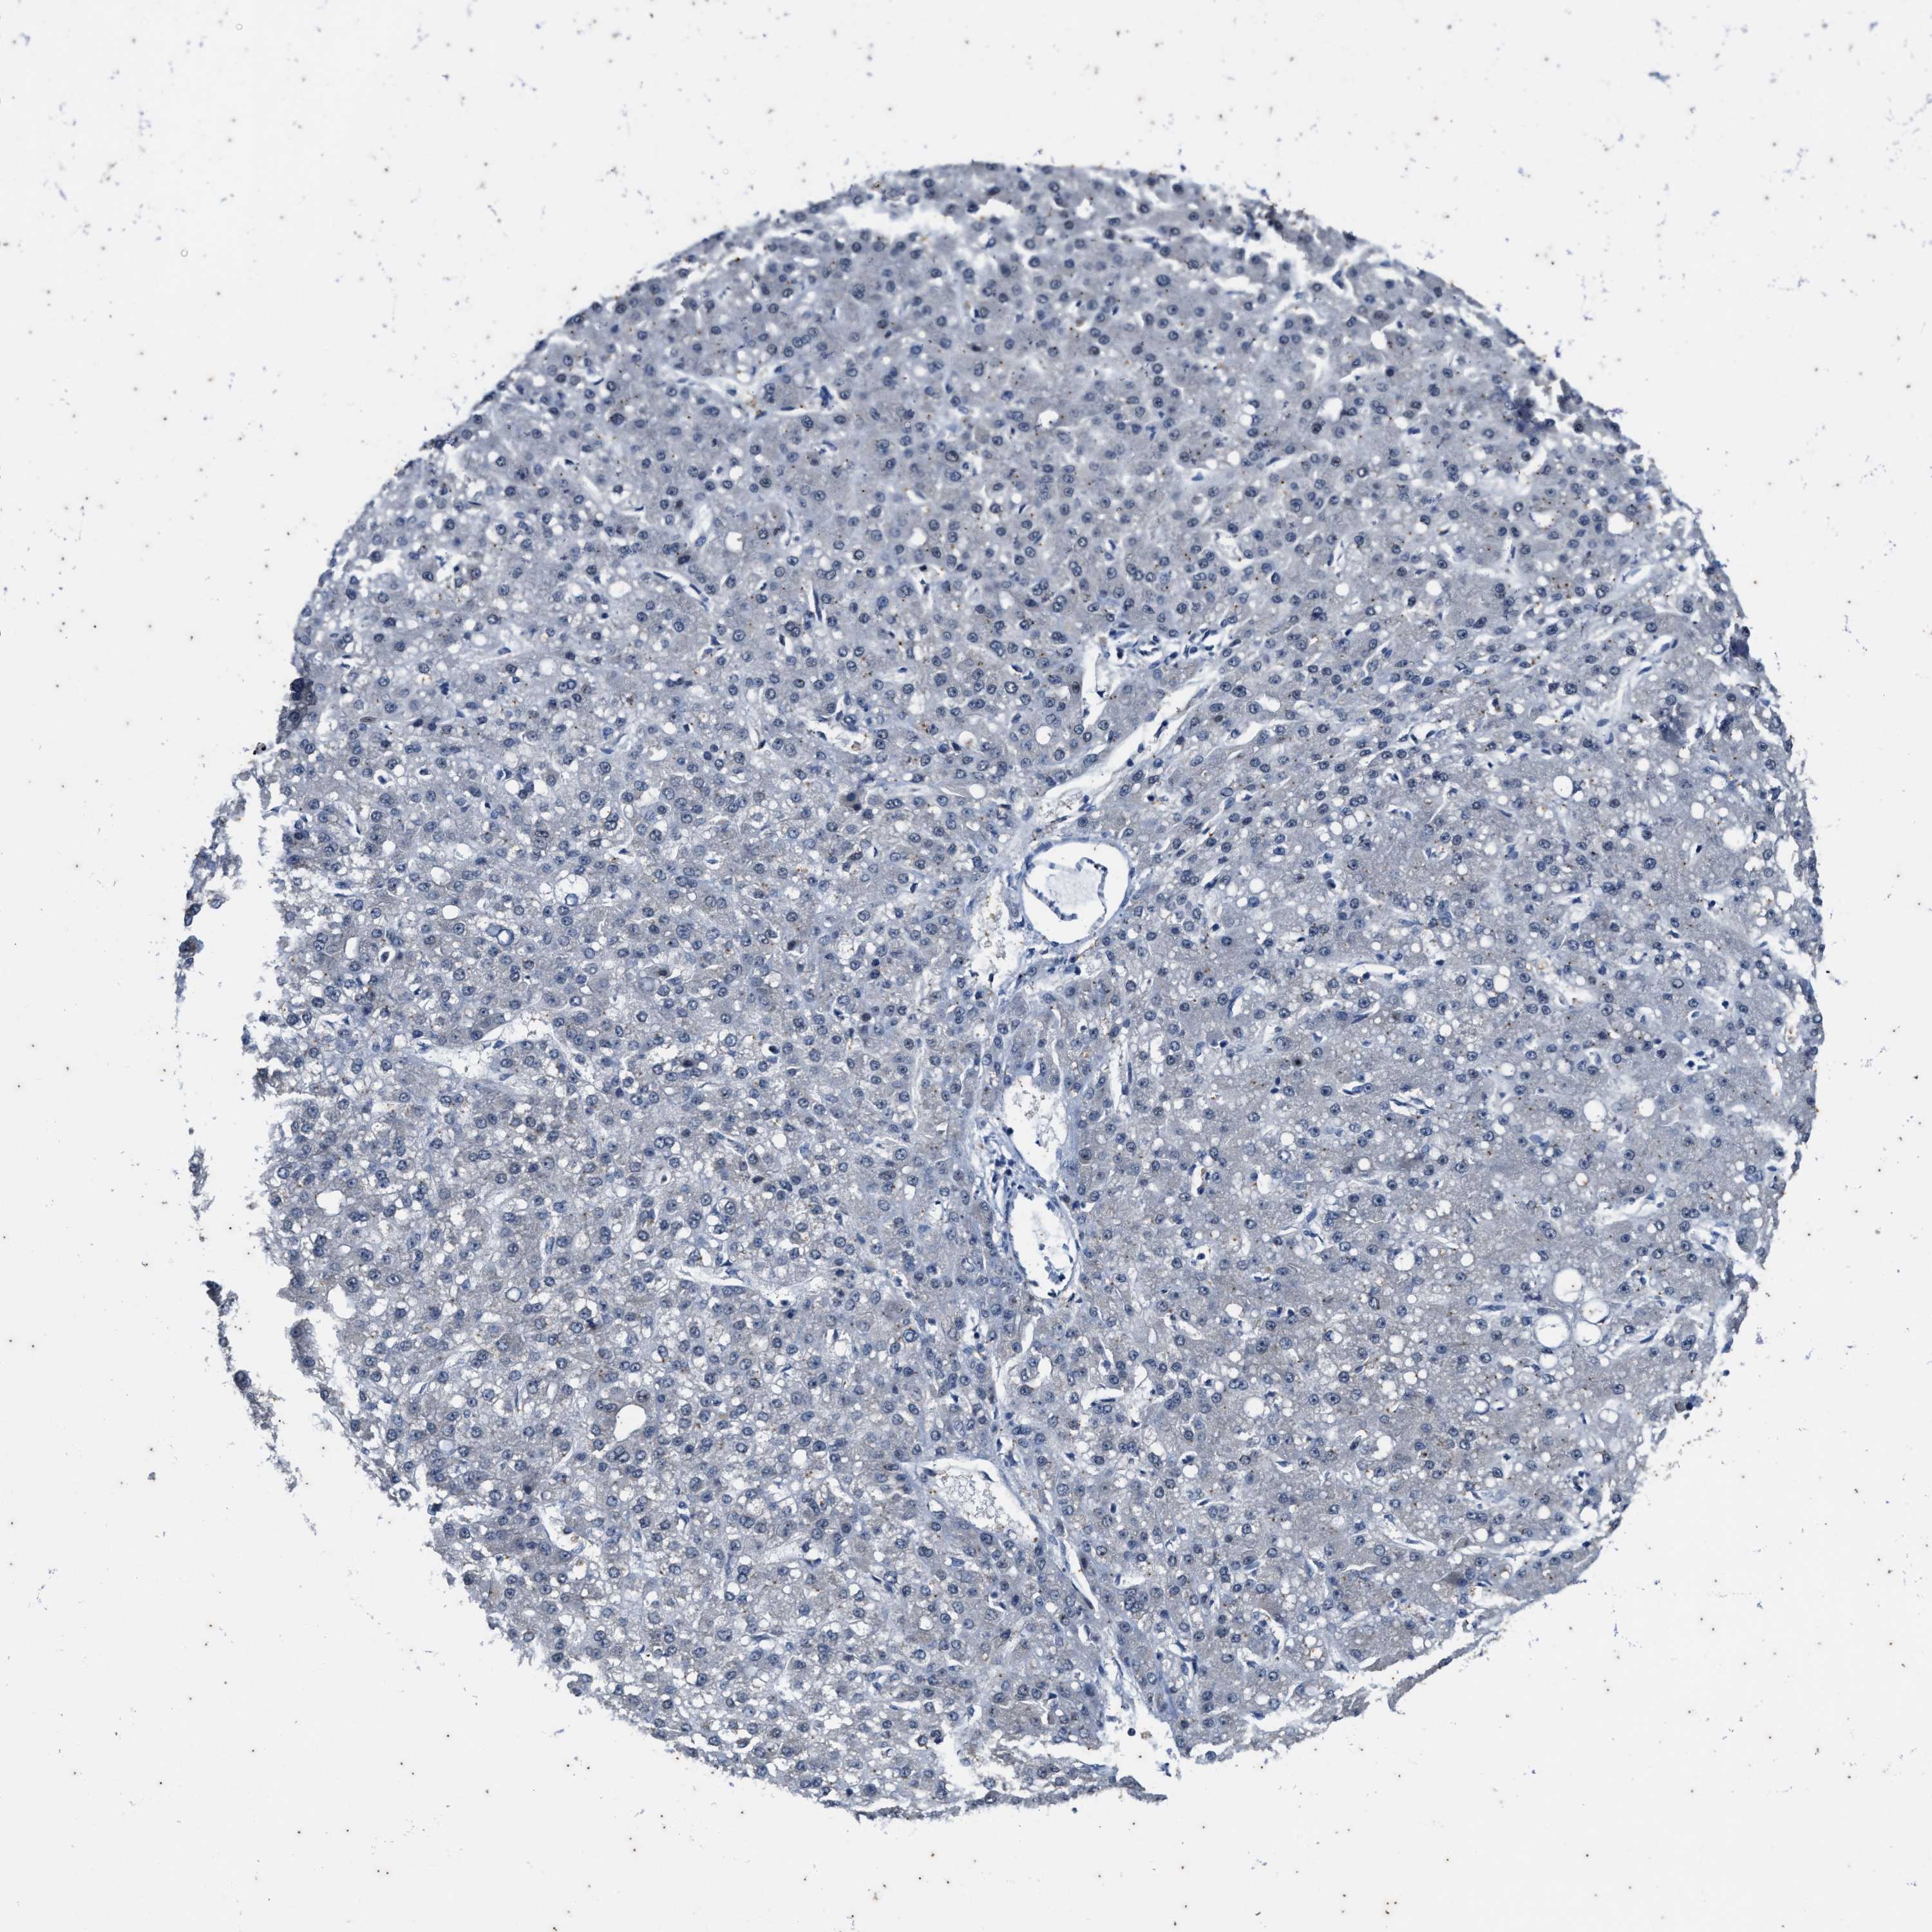

LIVER CANCER - Protein expressioni

A mouse-over function shows sample information and annotation data. Click on an image to view it in a full screen mode. Samples can be filtered based on level of antibody staining by selecting one or several of the following categories: high, medium, low and not detected. The assay and annotation is described here.

Note that samples used for immunohistochemistry by the Human Protein Atlas do not correspond to samples in the TCGA dataset.

Antibody stainingi

Antibody staining in the annotated cell types in the current human tissue is reported as not detected, low, medium, or high, based on conventional immunohistochemistry profiling in selected tissues. This score is based on the combination of the staining intensity and fraction of stained cells.

Each image is clickable and will lead to virtual microscopy that enables deeper exploration of all samples and also displays staining intensity scores, fraction scores and subcellular localization as well as patient and tissue information for each sample.

Antibody HPA021226

Staining

High

Medium

Low

Not detected

Intensity

Strong

Moderate

Weak

Negative

Quantity

>75%

75%-25%

<25%

None

Location

Nuclear

Cytoplasmic/membranous

Cytoplasmic/membranous,nuclear

Cholangiocarcinoma

Carcinoma, Hepatocellular, NOS